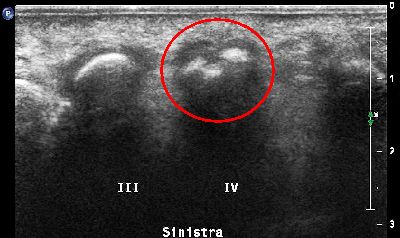

Sesamoide accessorio secondo dito (img. 01) Sesamoide accessorio secondo dito (img. 01)

Sesamoide accessorio secondo dito (img. 02) Sesamoide accessorio secondo dito (img. 02)